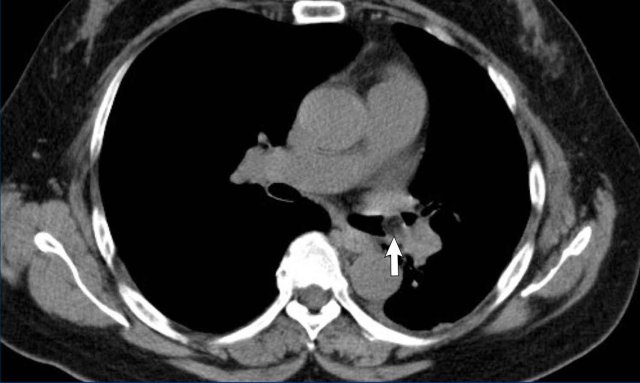

Image

Right-sided fibrosing mediastinitis in a 51 year old male, showing soft tissue density around the right main bronchus (arrow).

Same patient.

There are secondary signs of central airway and vessel

compression, with localized lung volume loss and interstitial thickening due to

edema.